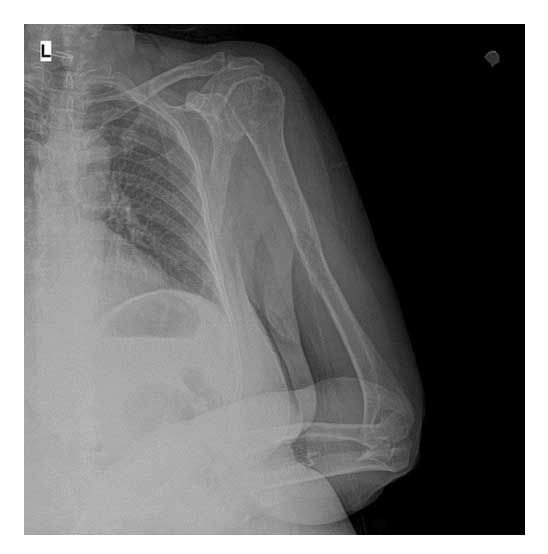

Vaka 5: Meme Kanseri Sol Kol (Humerus) Kemiği Metastazına Bağlı Kırık

Meme kanseri tanısı bulunan 73 yaş kadın hastada, sol kol kemiğinde (humerus) metastaza bağlı gelişen kırık cerrahi olarak başarılı şekilde tedavi edilmiştir. Hastanın ağrısı giderilmiş, kol fonksiyonu korunarak yaşam kalitesi artırılmıştır.

AAmeliyat Öncesi: Sol kol (Humerus) orta bölgede yeniklik ve ayrışmamış kırık görülmekte.